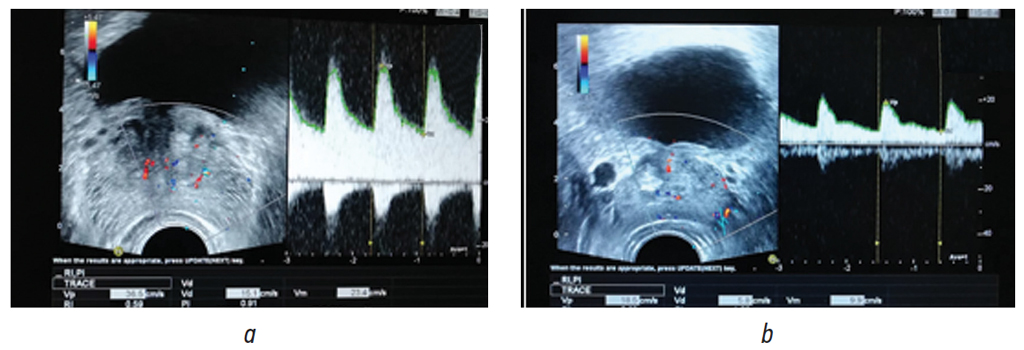

После проведенного лечения у пациентов ОГ была отмечена более выраженная динамика улучшения кровотока в предстательной железе по данным ТРУЗИ в доплеровском режиме к визиту 2, чем в ГС. К визиту 3 были выявлены статистически значимые различия во всех исследуемых показателях (p < 0,05). Пример доплерограммы пациента П., сделанной после лечения на визите 3, представлен на рис. 2.

Рис. 2. Пациент П. (основная группа). Трансректальное ультразвуковое исследование простаты в доплеровском режиме после лечения на визите 3: a — уретральные ветви артерии простаты; b — капсулярные ветви артерии простаты

Fig. 2. Patient P. (main group). Doppler TRUS of the prostate after treatment at visit 3: a – urethral branches of the prostate artery; b – сapsular branches of the prostate artery

В ряде исследований было показано, что у больных простатитом при выраженных фиброзных изменениях простаты и ДГПЖ имелось симметричное, диффузное ослабление васкуляризации, а при обострении простатита — симметричное, диффузное усиление васкуляризации. При этом было отмечено снижение гемодинамических показателей в ткани простаты по данным комплексного ТРУЗИ [28]. Результаты проведенного исследования соответствуют имеющимся в литературе данным: исходно в обеих группах были выявлены низкие показатели гемодинамки в предстательной железе. В группе пациентов, получавших стандартную терапию в сочетании с сеансами физиотерапии аппаратом «Смарт-Прост» в акрофазу хроноритма, была отмечена более выраженная динамика улучшения кровотока в предстательной железе по данным ТРУЗИ в доплеровском режиме, чем в ГС, о чем свидетельствуют более высокие показатели Vp, Vd, Vm, а также более низкие значения RI и PI. К визиту 3 были выявлены статистически значимые различия во всех исследуемых показателях (p < 0,05).